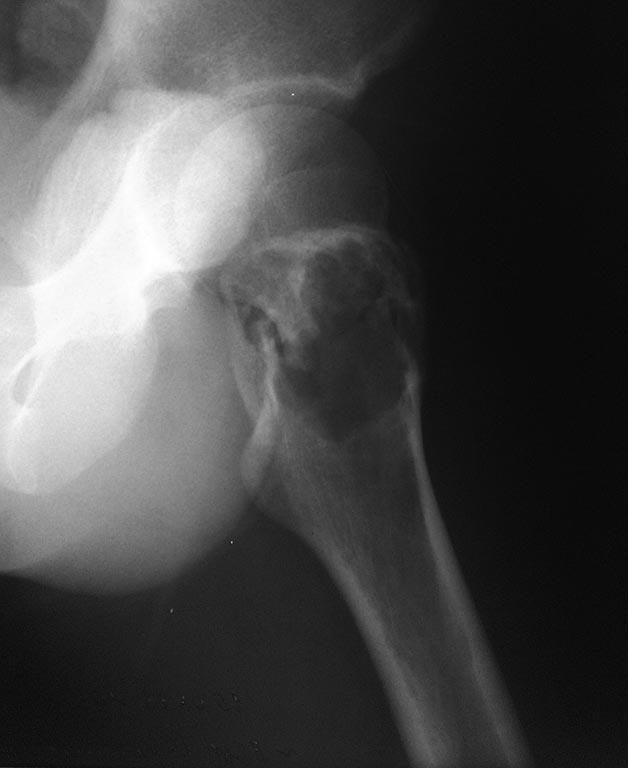

На представленной R-грамме левого тазобедренного сустава–выявляется

деструктивная полость в вертельной области левой бедренной кости

нарушение костной структуры с образованием костной полости с

тонкостенными перегородками.Границы полости крупно ячеистые.

Госпитализирован с предварительным диагнозом: Остеобластокластома

вертельной области левой бедренной кости. Закрытый патологический

чрезвертельный перелом левой бедренной кости?